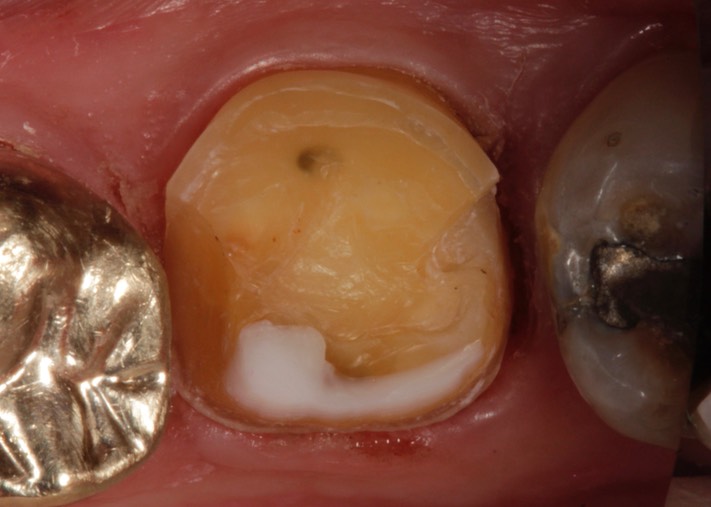

Photos of Clinical Operations

Larry Fujioka #18 prep